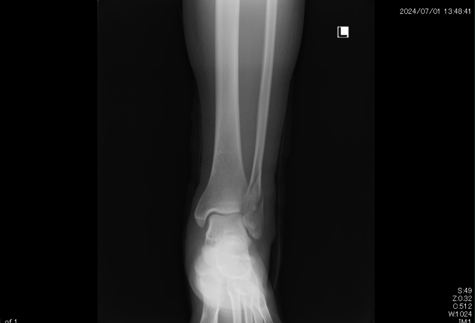

●左腓骨遠位端骨折

足首を捻り外側の骨 足首に近いところを骨折をしてしまいました。整形外科での診断後 手術の予定が決まりそれまでの間シーネ固定することになりましたが、手術療法に不安があり保存療法(自然療法)をインターネットで検索中当院のホームページにたどりつきました。

実は患者さんは他府県に住まれていたので近隣の他の整形外科でセカンドオピニオンを得ることを提案しましたが、どこの先生方も手術療法をすすめました。

結果的に2時間以上かけて当院に来院。保存療法で治療することになりました。コンパクトな固定ギプスと患部の血行を促進 超音波治療により腫れも痛みも軽減。経過良好でした。

4か月後には予定していた巡礼の旅 50kmの道を完歩することができました。なによりも手術の痕を残さず自然療法で完治したことに喜んでもらえました。